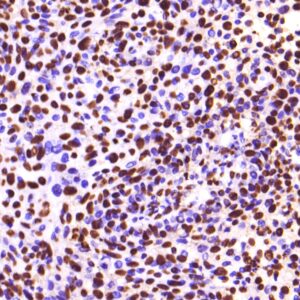

BioGenex offers fluorescein-labeled oligonucleotide probes to detect DNA or RNA using In situ Hybridization (ISH). These probes allow quantitative detection of specific DNA/RNA sequences in their native form within the cells of formalin-fixed paraffin-embedded (FFPE) tissue sections. These probes offer reliable, highly sensitive, and easy-to-perform DNA and RNA ISH assays when used with the BioGenex ISH Detection Systems.